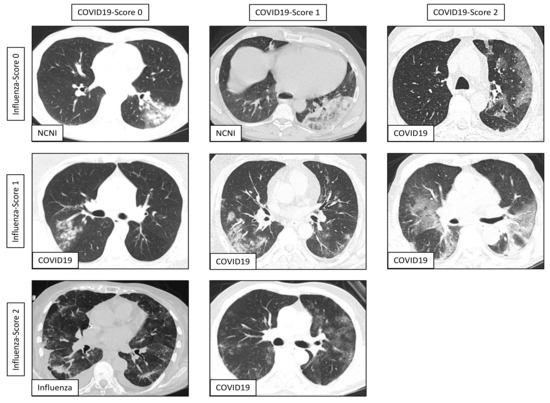

| COVID19-Reading-Score 0 [n] | 5 | 40 | 45 |

| COVID19-Reading-Score 1 [n] | 18 | 19 | 16 |

| COVID19-Reading-Score 2 [n] | 55 | 6 | 1 |

| Influenza-Reading-Score 0 [n] | 25 | 19 | 21 |

| Influenza-Reading-Score 1 [n] | 46 | 31 | 35 |

| Influenza-Reading-Score 2 [n] | 7 | 15 | 6 |